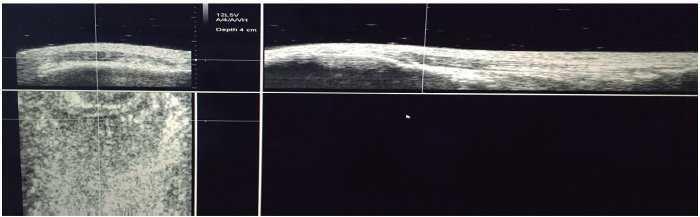

Totes les valoracions es van fer al matí, a l’inici de la pretemporada, els jugadors en edats formatives el dia 18 d’agost, i els jugadors professionals el 25 d’agost. Realitzà l’exploració el mateix expert en ultrasonografia i UTC (GH) d’ambdós tendons rotulars, mitjançant ecografia en mode B amb un transductor lineal de 7-10 MHz (SmartProbe 10L5; Terason 2000, Teratech, EUA) muntat sobre el dispositiu que mou el transductor de forma automàtica en l’eix perpendicular del tendó i que grava les imatges transversals a intervals de 0,2 mm sobre una distància de 12 cm (600 imatges axials) (fig. 1). El dispositiu estandarditzà l’angle d’inclinació de la sonda, el guany, el focus i la profunditat. La captura de les imatges i els mesuraments d’UTC es realitzaren d’acord amb un protocol estandarditzat, aplicat en altres estudis6.

Figura 1 Aparells utilitzats per fer els mesuraments. Dispositiu UTC.

El jugador es situà assegut amb el genoll flexionat a 90° i amb el peu recolzat en una superfície elevada. El dispositiu es col·locà paral·lel a l’eix llarg del tendó rotular des de la inserció distal a la tuberositat tibial anterior fins a la inserció proximal en el pol inferior de la ròtula. S’aplicà gel entre la pell, el suport de silicona i entre aquest suport i la sonda d’ultrasons abans de fer l’exploració (fig. 2).